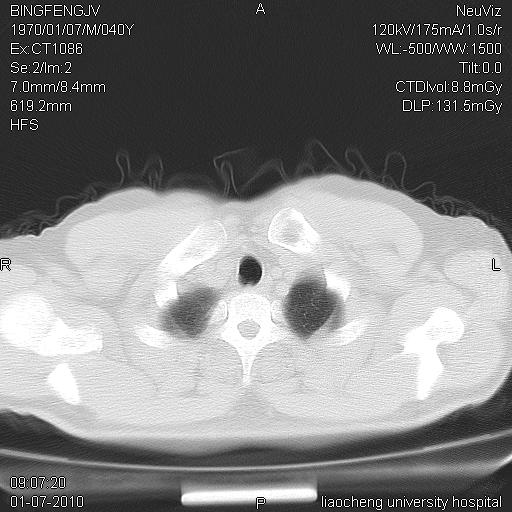

标题: CT23764B:男 40 肺部CT [打印本页]

标题: CT23764B:男 40 肺部CT

治疗2周后

考虑左肺上叶近胸膜下炎症并肺气囊形成。